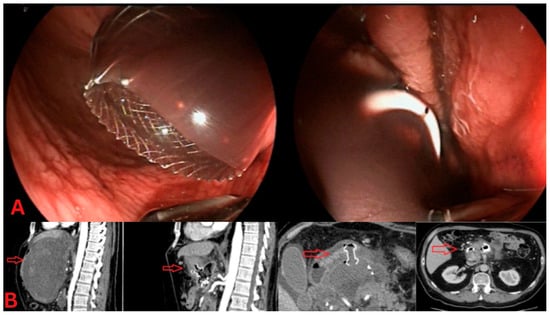

Figure 1. Direct endoscopic necrosectomy (DEN). (A) Endoscopic view: This image shows direct endoscopic necrosectomy (DEN) from walled-off pancreatic necrosis (WOPN). The necrotic tissue is visualized through the endoscope, with a clear opening into the cavity containing necrotic material. (B) CT imaging: The left CT scan shows a sizeable peripancreatic collection before DEN, with encapsulated fluid and necrotic debris (red arrow). The CT scan on the right demonstrates the post-procedural imaging after DEN, showing a significant reduction in the collection and improved drainage.